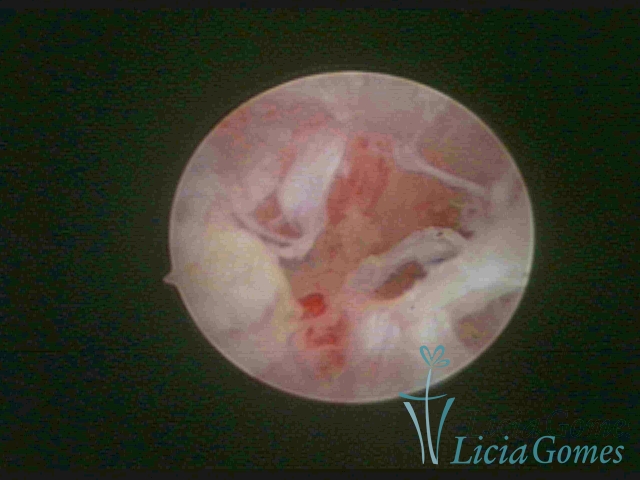

FIBROUS SYNECHIA

Uterine synechiae are scars (adherence) between the surface of the uterine walls, which may occur after the surgical procedure, uterine curettage, or after an inflammatory process in the uterine cavity (endometritis), which may lead to menstrual changes, infertility and obstetric complication such as abortion and premature birth.